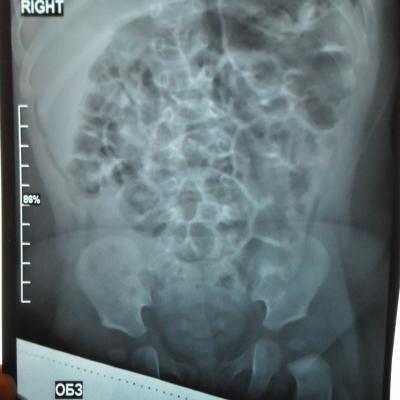

Моему ребенку 1 год 1 месяц. Во время беременности у плода было обнаружено увеличение лоханки слева - 9мм. Далее по результатам УЗИ после рождения максимальное увеличение достигало 17 мм. В 5 месяцев проходили урологическое обследование, результаты цистографии: мочевой пузырь округлой формы. Контуры ровные. ПМР нет. ЭЭД-1,2МЗВ; урографии: рентгеноконтрастных теней конкремента нет, почки в типичном месте, размеры сохранены, структура ЧЛК справа не изменена, слева пиелоэктазия, подвижность допустима, функция сохранена, ЭЭД – 0,4 МЗВ. По последнему УЗИ (1 год) увеличение лоханки слева - 28 мм. Мочеточники и сама почка в норме. Результаты анализов мочи за этот год хорошие (сдавали ежемесячно). В чем могут быть причины данного явления и чем это грозит малышу?